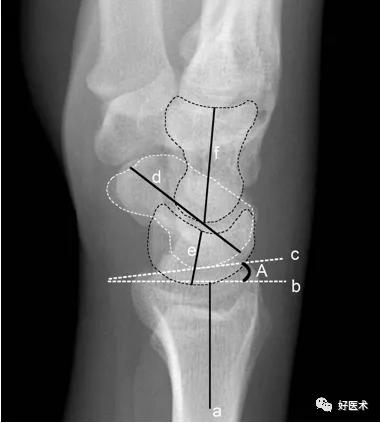

一例经舟骨月骨周围脱位患者,知识点:

3影像学上,可以用Gilula线评价桡腕及腕中关节,如此弧线平滑、无中断,说明各腕骨位置关系正常,否则提示有异常

X线正位片中,Gilula线中断则提示腕关节异常

各腕骨间隙大于等于2mm,且与健侧不同,提示异常